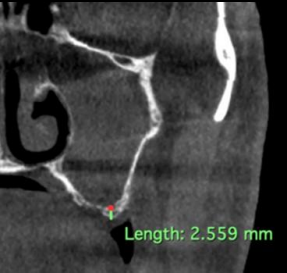

A 43-year-old male patient presented to our Oral and Maxillofacial Surgery unit with the chief complaint of missing upper posterior teeth bilaterally, expressing a desire for implant-based rehabilitation on both sides. On thorough examination, the patient disclosed that the teeth were lost approximately one year ago due to extensive carious lesions. To assess the residual bone height in the regions of teeth 2, 3, 4, and 13, 14, 15, a comprehensive radiographic investigation was conducted. Cone beam computed tomography (CBCT) revealed that the sinus floor was in close proximity to the alveolar crest, with the height of 2.5mm at the deepest point of pneumatisation.

Figure 1: Coronal imaging delineates the pathology most consistent with odontogenic maxillary rhinosinusitis.

Figure 1